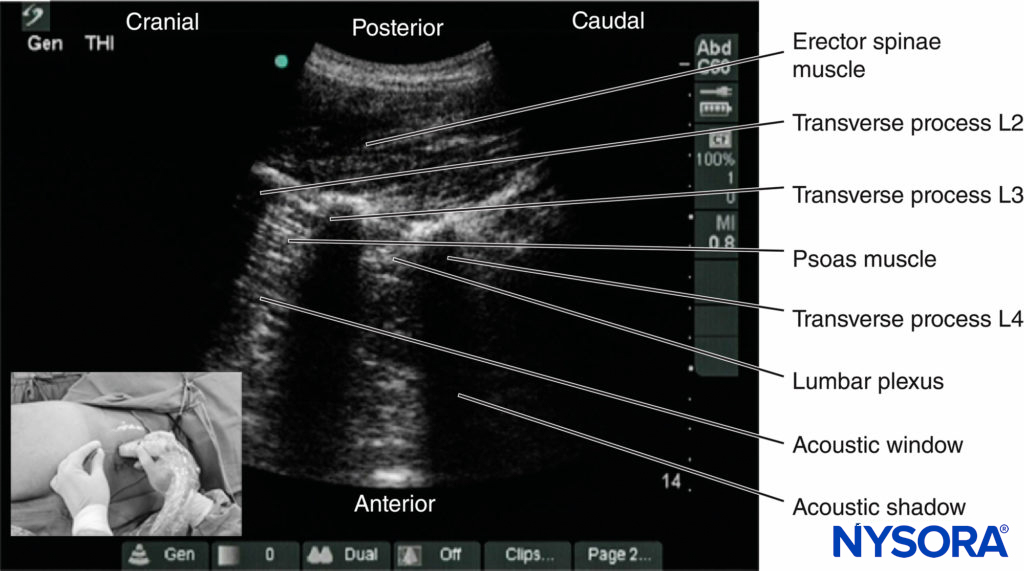

A liberal amount of ultrasound gel is applied to the skin over the lumbar paravertebral region for acoustic coupling. To simplify image orientation, irrespective of the side imaged, the orientation marker of the US transducer is directed cranially during a sagittal scan and laterally (outward) during a transverse scan. For a sagittal scan (Figures 9, 10, 11, and 12), the US transducer is positioned over the sagittal scan line (see Figure 9a) with its orientation marker directed cranially. For a transverse scan (Figures 9,10, 13, and 14), the US transducer is positioned 4 cm laterally to the midline along the intercristal line and just above the iliac crest (see Figure 9b). The transducer is also directed slightly medially (paramedian transverse oblique scan [PMTOS]; see Figure 9b) so as to produce a transverse oblique view of the lumbar paravertebral region (see Figures 13 and 14).

During a PMTOS, the US beam can be insonated either at the level of the transverse process (PMTOS-TP; see Figures 10b and 13 or through the intertransverse space at the level of the articular process (PMTOS-AP: see Figures 10c and 14). Alternatively, a transverse scan can be performed by placing the US transducer more anteriorly in the flank and above the iliac crest (Figures 15, 16, 17, 18, and 19), as described by Sauter and colleagues with the “shamrock method.”

On a sagittal sonogram, the lumbar transverse processes are identified by their hyperechoic reflection and an anterior acoustic shadow (see Figures 11 and 12), which is typical of bone. The acoustic shadow of the transverse processes produces a sonographic pattern referred to as the “trident sign” (see Figures 11 and 12) because of its similarity in shape to a trident (in Latin, tridens or tridentis).

The psoas muscle is visualized through the acoustic window (see Figures 11 and 12) of the trident as multiple longitudinal hyperechoic striations against a hypoechoic background typical of muscle (see Figure 11). The lumbar plexus nerves are seen as longitudinal hyperechoic structures in the posterior aspect of the psoas muscle (see Figure 11) One should note that not all hyperechoic shadows or striations within the psoas muscle are nerves because the psoas muscle contains intramuscular tendons, which also produce hyperechoic shadows (Figure 20).

After it exits the intervertebral foramen, the lumbar nerve root does not enter the psoas muscle directly opposite the intervertebral foramen from which it emerges (see Figure 14), but takes a steep caudal course (see Figure 14), entering the psoas muscle at the vertebral level below to join the lumbar plexus. The lumbar plexus is seen as a separate hyperechoic structure within a hypoechoic space, the psoas compartment, in the posterior aspect of the psoas muscle (see Figure 14). In a transverse sonogram produced by the shamrock method (see Figure 15), the psoas, erector spinae, and quadratus lumborum muscles are also clearly visualized (see Figures 16, 17, 18 and 19). The anatomical arrangement of the three muscles around the transverse process—that is, the psoas muscle lying anteriorly, the erector spinae muscle lying posteriorly, and the quadratus lumborum muscle lying at the apex (see Figure 16)—produces a sonographic pattern that has been likened to the shape of a “shamrock,” with the muscles representing its three leaves. The lumbar nerve root may also be visualized close to the angle between the vertebral body and the transverse process (see Figure 16) and the lumbar plexus within the posterior aspect of the psoas muscle, typically about 2 cm anterior to the transverse process (see Figures 17 and 18). From this position, if the transducer is gently tilted caudally, the acoustic shadow of the L4 transverse process disappears, and the US beam is now insonated through the intertransverse space and at the level of the articular process of the L4 vertebra, similar to that seen with a PMTOS-AP (see Figure 17). As a result, apart from the psoas, erector spinae, and quadratus lumborum muscles, the intervertebral foramen and lumbar plexus may also be visualized (see Figure 17).

3. The Shamrock Method

Sauter and colleagues recently described an alternative approach for USG LPB, which they refer to as the “shamrock method (Figure 24b).” As described above, a transverse scan is performed at the flank and immediately above the iliac crest, with the patient in the lateral position and with the side to be blocked uppermost (see Figures 15a,b and 24b). Once the sonographic pattern of the “shamrock” is obtained at the level of the L4 transverse process (see Figure 16), the US transducer is tilted slightly caudally until the acoustic shadow of the transverse process is no longer visualized (see Figure 17).

This view represents the transverse view of the anatomy relevant for LPB through the L4–5 intertransverse space. A line is then drawn on the patient’s back extending from the center of the medial end of the IS transducer to the midline (back). A nerve block needle is inserted 4 cm from the midline along this line (Figure 28) and gradually advanced anteriorly under real-time US guidance (in-plane needle insertion; Figure 29a) until the needle tip is close to the L3 nerve root. Nerve stimulation should be used in conjunction with US to confirm correct needle placement, after which 20–30 mL of ropivacaine or levobupivacaine 0.5% is injected slowly while visualizing the perineural spread of the drug in the posterior aspect of the psoas muscle (Figure 29b).